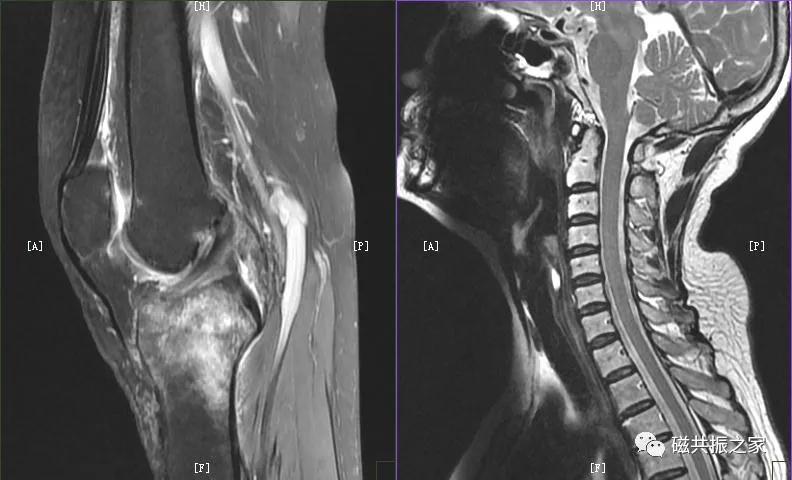

人体很多部位在不同的年龄阶段( 如脊柱、四肢关节等 ) 或特殊时期(如孕期垂体等) MRI信号是具有差异的 。

为了减轻相应的伪影,很多部位的相位编码方向是置于扫描部位的长轴方向上的,如关节、脊柱等部位,并且如你细心就会发现几乎所有部位的横轴位DWI的相位编码方向都是前后方向。